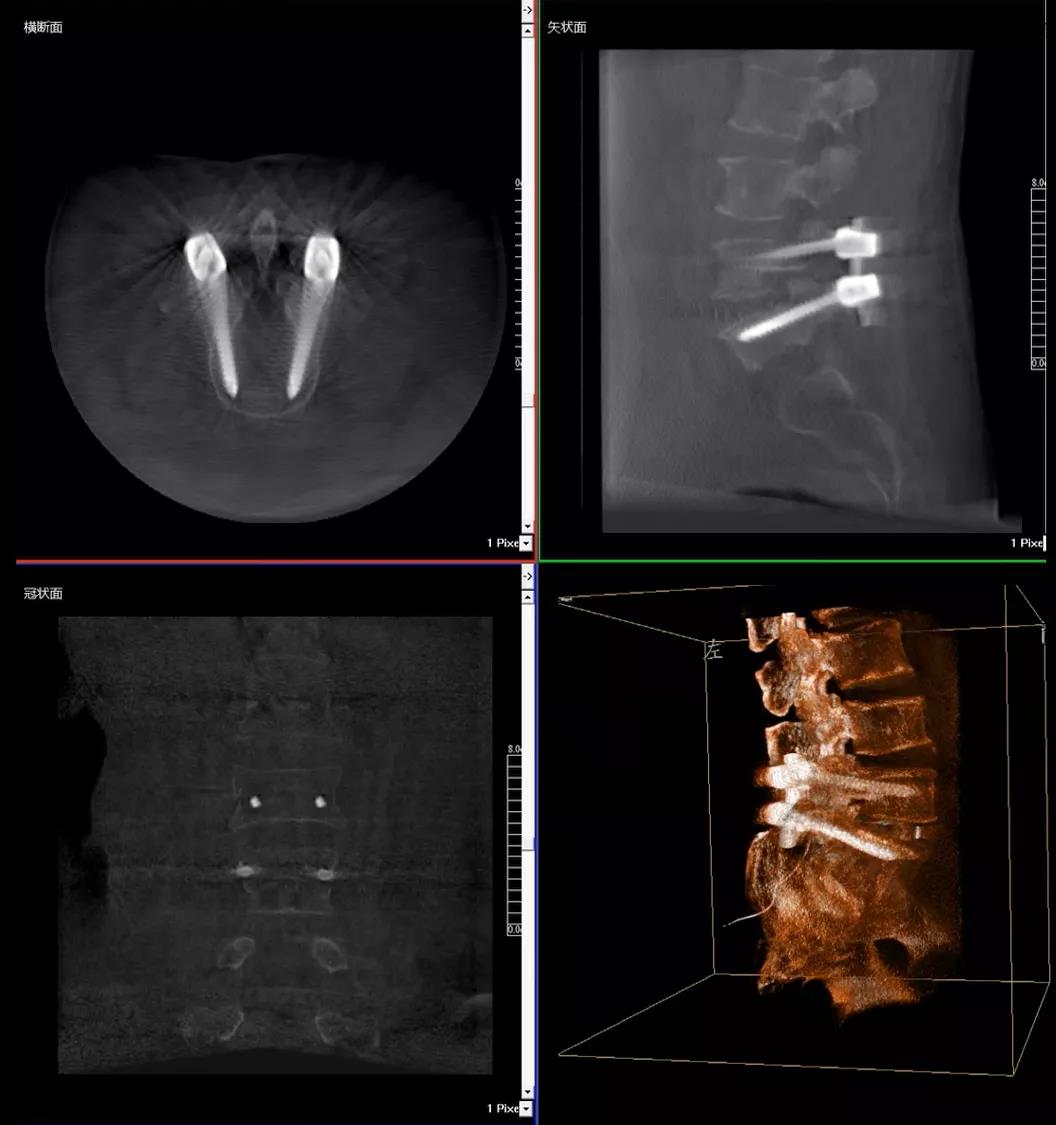

術中快速生成橫斷面、矢狀面、冠狀面斷層圖像和三維立體圖像